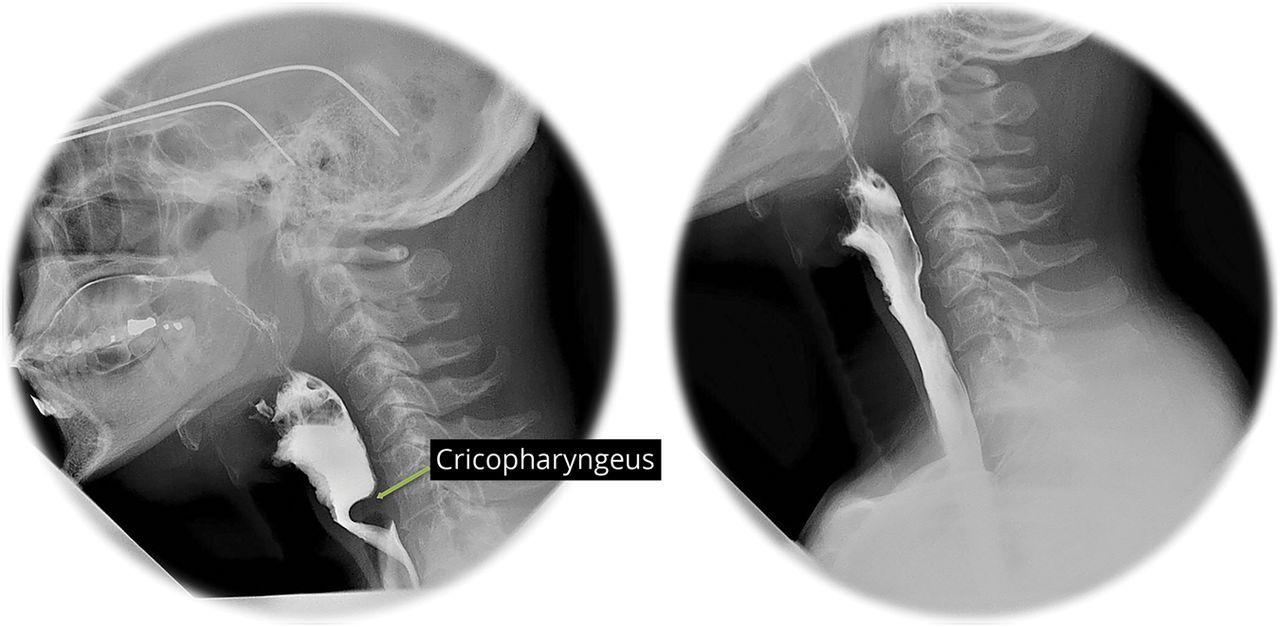

实验室检查是非凡的肌酸激酶升高550年(正常52 - 336 U / L)。血液测试包括肝功能、肾功能、促甲状腺激素、乳酸水平是正常的。肌炎自身抗体面板和乙酰胆碱受体结合抗体也正常。视频吞下的一项研究显示适度口咽吞咽困难明显突出的cricopharyngeus肌肉(图1)。肺功能测试显示正常的肺活量,但最大呼气压力下降。夜间血氧定量法显示轻度睡眠障碍性呼吸的证据。

cricopharyngeus video-swallow钡显示显著突出,涵盖超过一半的腔的直径(左),显著改善后环咽的肌切开术(右)。